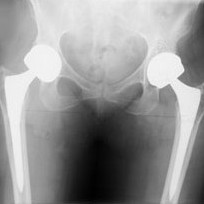

Most likely the cause is from the friction and rubbing together of the two metal surfaces of your hip implant. Small dust-like particles of the metals sheer off and spread through your body via your bloodstream. During revision surgery, doctors are finding dark discolored fluid and dead tissue in the body’s joint area surrounding the metal on metal hip. All patients with recalled metal on metal hip replacements should be evaluated for the level of serum cobalt and chromium in their system.